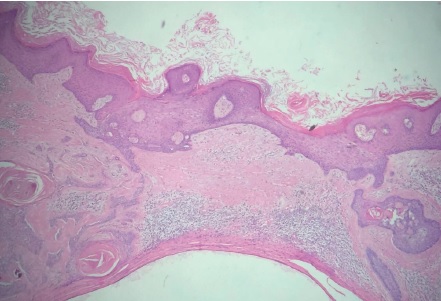

Paciente do sexo feminino, 65 anos, parda, queixando-se de prurido no couro cabeludo há um mês. Ao exame observava-se na região occipital: placa verrucosa, discretamente eritematosa medindo cerca de 2,5cm no seu maior eixo (Figuras 1 e 2). Segundo a paciente, desde o nascimento apresentava lesão assintomática no couro cabeludo que, há um mês, tornara-se pruriginosa. Optou-se por biópsia incisional da lesão e exame histopatológico, o qual evidenciou carcinoma basocelular nodular (Figura 3). Realizada então a excisão completa da lesão com margem, cujo exame histopatológico revelou: nevo sebáceo associado a siringocistoadenoma papilífero, adenoma tubular apócrino, triquilemoma (Figuras 4 a 7) e fibrose dérmica cicatricial.

O NSJ, conhecido também como nevo organoide, é mais incidente no couro cabeludo, podendo apresentar-se na face e menos comumente nos membros.3,5 Ocorre em aproximadamente 0,3% dos indivíduos, sem predileção por gênero. A lesão em geral está presente ao nascimento e apresenta-se como placa bem delimitada constituída por múltiplas pápulas confluentes de coloração amarelo-alaranjada ou amarelo-acastanhada, predominantemente no couro cabeludo, onde cursa com alopecia no local da lesão.3 Apresenta distribuição bimodal: durante a puberdade, quando sua superfície torna-se espessada e verrucosa por estímulos hormonais aos componentes écrinos e apócrinos, podendo, na fase adulta, a lesão se tornar nodular com a ocorrência de ulcerações e crostas. A possibilidade de surgimento de neoplasias secundárias nessa fase varia de dez a 30%, sendo as principais o carcinoma basocelular, o siringocistoadenoma papilífero (ambos observados nessa paciente) e o tricoblastoma.3